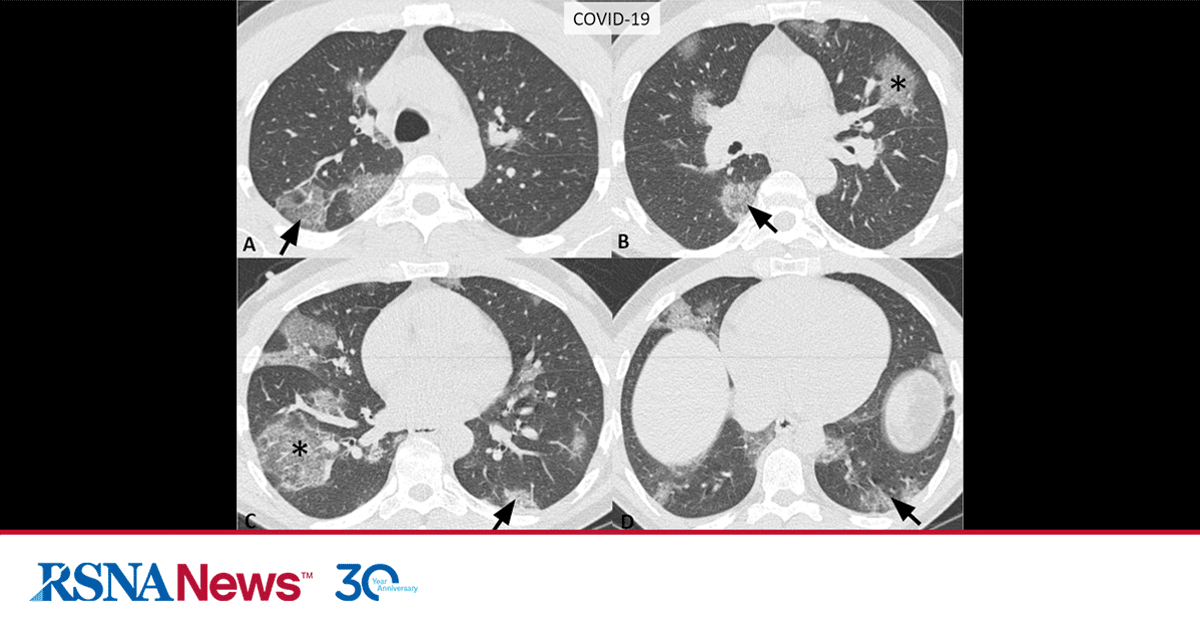

Covid 19 Infographic Rsna Rsna has developed partnerships with key organizations to launch the rsna international covid 19 open radiology database (ricord). we have put in place a pathway for radiology sites. Covid 19 radiography database (winner of the covid 19 dataset award by kaggle community) a team of researchers from qatar university, doha, qatar, and the university of dhaka, bangladesh along with their collaborators from pakistan and malaysia in collaboration with medical doctors have created a database of chest x ray images for covid 19. It is made freely available to the machine learning community as a research and educational resource for covid 19 chest imaging. pixel level volumetric segmentation with clinical annotations was performed by thoracic radiology subspecialists for all covid 19–positive thoracic ct scans. Find direct access to new research on diagnostic imaging of covid 19 published across rsna journals.

Consensus Covid 19 Reporting Rsna It is made freely available to the machine learning community as a research and educational resource for covid 19 chest imaging. pixel level volumetric segmentation with clinical annotations was performed by thoracic radiology subspecialists for all covid 19–positive thoracic ct scans. Find direct access to new research on diagnostic imaging of covid 19 published across rsna journals. Infographic: impact of covid 19 pandemic on radiology learn more about the financial fallout, disruption of normal operations, safety concerns and positive changes. To address this unmet need, the rsna and society of thoracic radiology (str) collaborated to develop the rsna international covid 19 open radiology database (ricord). this database is the. The impact on health care institutions during the coronavirus disease 2019 pandemic has been considerable, with exhaustion of institutional and personal protective equipment resources during local outbreaks and crushing financial consequences for many institutions. Structured reporting for chest x ray and ct findings in the assessment of covid 19. a collection of free peer reviewed covid 19 cases for the global radiology community. join the conversation and get peer to peer support in our online community.